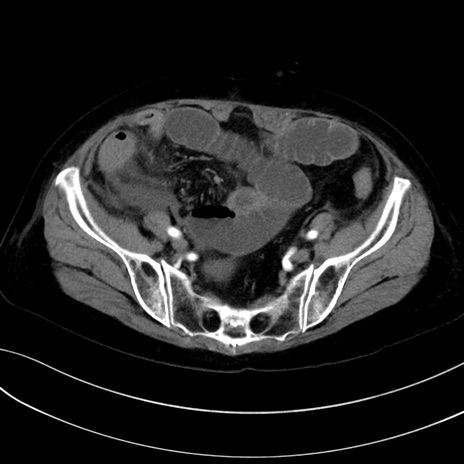

症例13 CT(横断像)1日半後